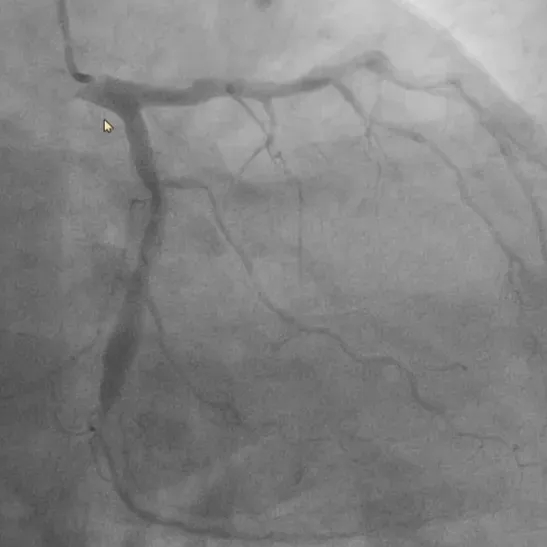

首例患者为一名患有冠心病的52岁男性,经术前冠脉造影检查显示左冠前降支和回旋支均有80%以上狭窄病变,需进行支架植入治疗,在与患者充分沟通并签署知情同意书后,手术顺利实施。

基线造影—左冠回旋支

本次手术涵盖了机器人辅助下的冠脉造影及支架植入全流程。窦克非主任医师通过机器人系统,成功完成了导管全程递送及钩冠、导丝通过病变、球囊预扩张、支架精准释放及球囊后扩张等关键步骤。手术中最引人注目的是机器人系统的全流程辅助和多通道多器械协同操控能力。医生可根据病变特点和手术需要,选择导丝和导管独立操控或同步联动,双导丝和双球囊/支架导管同时操控,大幅提升了操作效率。

术后即刻造影显示,支架扩张、贴壁良好无残余狭窄,TIMI血流3级,手术效果显著。

术后造影—左冠回旋支